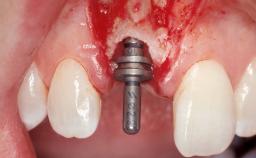

Late Placement of an Implant in a Maxillary Left Central Incisor Site

A 36-year-old female patient was referred for the replacement of the upper left central incisor (tooth 21), which had fractured. Although the tooth had been asymptomatic for many years, the crown began to loosen, at which time she presented to her dentist for an assessment. Teeth 21 and 22 had both been endodontically treated many years previously. She was a healthy individual and a non-smoker.

The crown of tooth 21 was splinted to the adjacent teeth with composite resin, and the gingiva was inflamed.